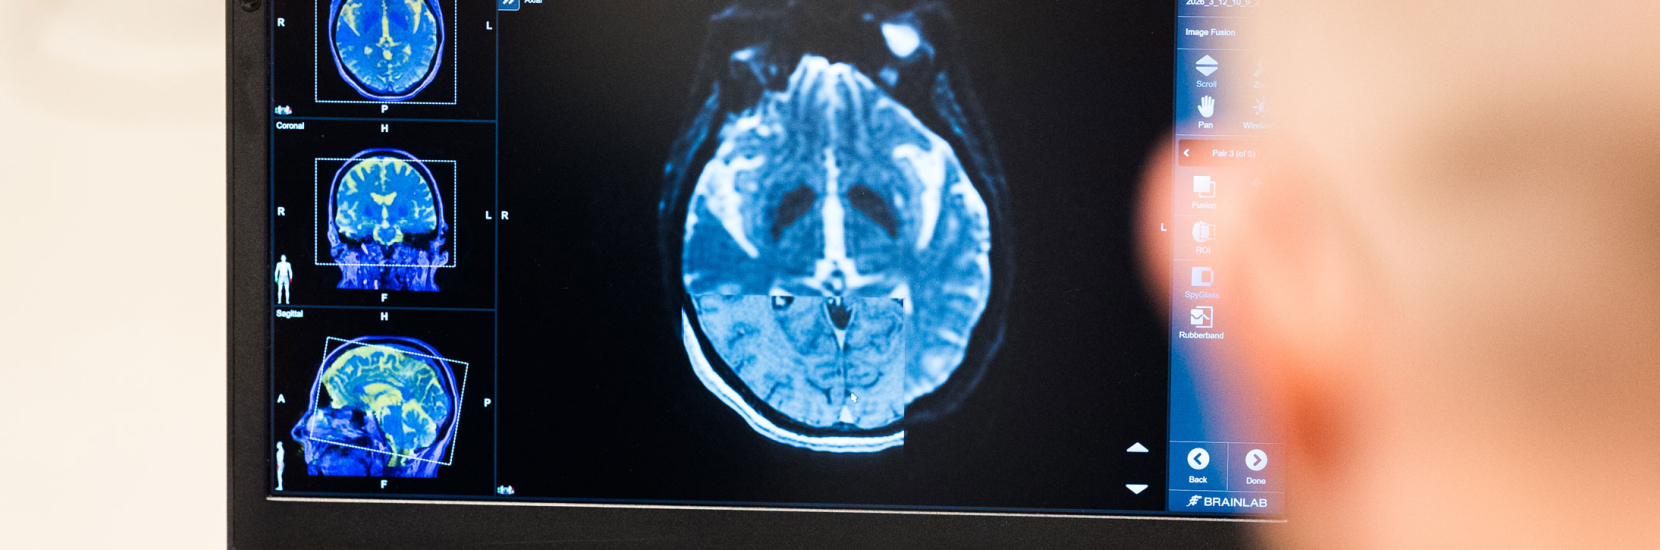

A particular focus was placed on modern technologies such as image-guided programming and wearable sensor systems for therapy monitoring.